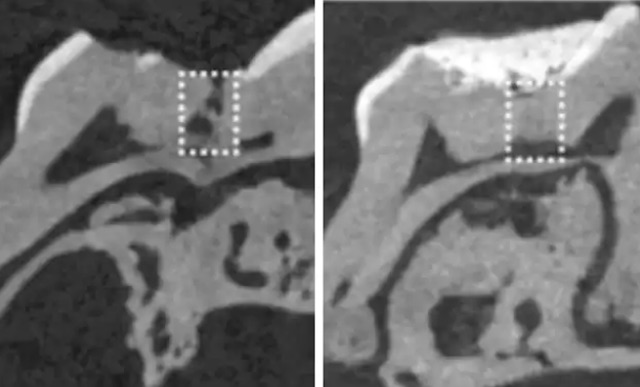

Using biodegradable collagen sponges to deliver the treatment, the team applied low doses of small molecule glycogen synthase kinase (GSK-3) inhibitors to the tooth. They found that the sponge degraded over time and that new dentine replaced it, leading to complete, natural repair. Collagen sponges are commercially-available and clinically-approved, again adding to the potential of the treatment’s swift pick-up and use in dental clinics.